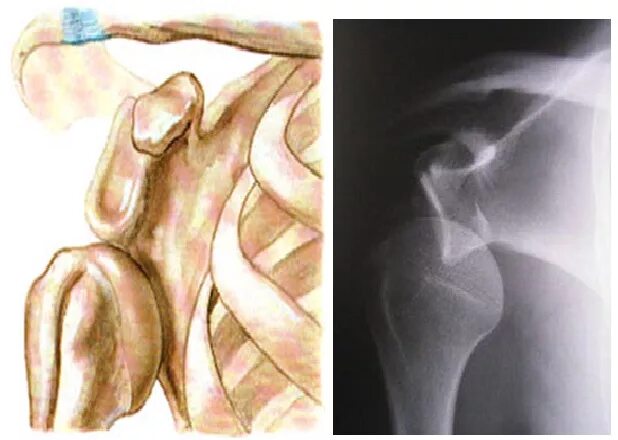

Нестабильность плечевого сустава мкб